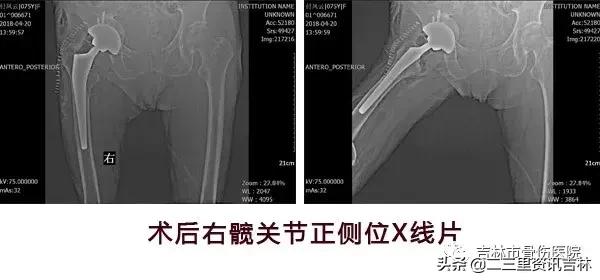

患者入院后给予常规检查,经三级医师查房,临床诊断确诊,经过科内及院内医生会诊,查无明显手术禁忌症后在腰硬+全麻下行“右侧全髋关节置换术后假体松动关节翻修术”,术中我们沿原手术切口瘢痕切开皮肤、皮下及深筋膜,切开关节囊,活动髋臼杯见髋臼杯假体活动,依次取出内衬及髋臼杯,见髋臼内陷,髋臼壁薄弱,原有的髋臼结构及承重结构已破坏、消失,我们取同种异体骨材料用咬骨钳处理成大小不一的若干个骨块,万古霉均匀素涂后倒入髋臼处,*压打**植骨,抹平后用髋臼锉处理髋臼,脉冲冲洗,外用万古霉素,然后根据术前测量的髋臼大小,置入型号为Φ64/32mm3D打印金属髋臼,活动髋臼较稳定,并以3枚螺钉固定,放入内衬,活动内衬较稳定。活动原有股骨柄假体见略有微动,用打拔器取出原有股骨柄,髓腔挫扩髓,植入型号为8#的股骨柄,安装32mm球头。复位,试行关节外展、内收、前屈、后伸、旋转各方向活动,见关节稳定性良好,纵向牵拉,活动度约1厘米。对比健侧,双下肢基本等长。逐层缝合,术终。术后给予抗感染、消肿、抗凝关节功能松动练习等对症治疗,术后患者自诉疼痛明显减轻,现患者及其家属对当前治疗表示满意。

X线片示:右侧人工髋关节置换术后影像,髋臼内陷,髋臼壁薄弱,原有的髋臼结构及承重结构已破坏、消失,股骨柄下沉,余未见明显异常。